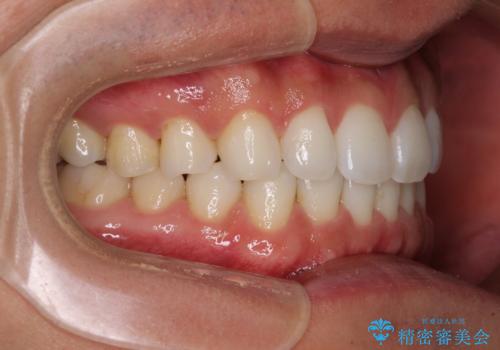

- 上下前歯のデコボコを気にして来院された患者様です。

以前矯正をした後戻りということで、歯列不正はそれほど大きくなかったため、インビザライン・ライトを用いて矯正治療を行うこととしました。

1日22時間以上しっかりと装着してくださったので、半年かからずに治療を終えることができました。